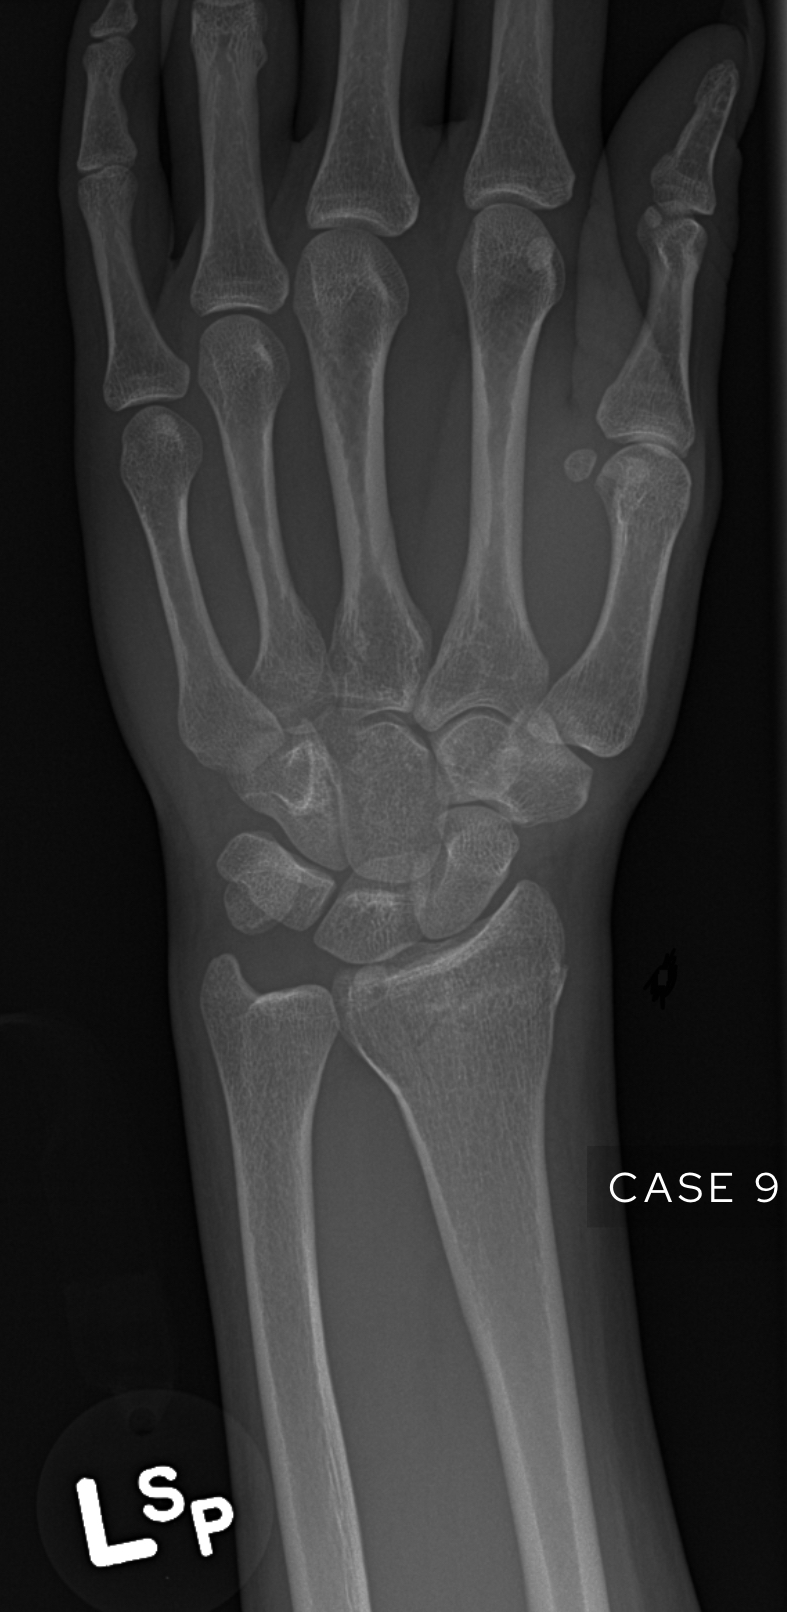

Case 9

A female in their 70s presents with wrist pain after a fall onto an outstretched hand (FOOSH). Assess the following wrist X-Ray. What is the most likely diagnosis?

Choose from one of the following options: